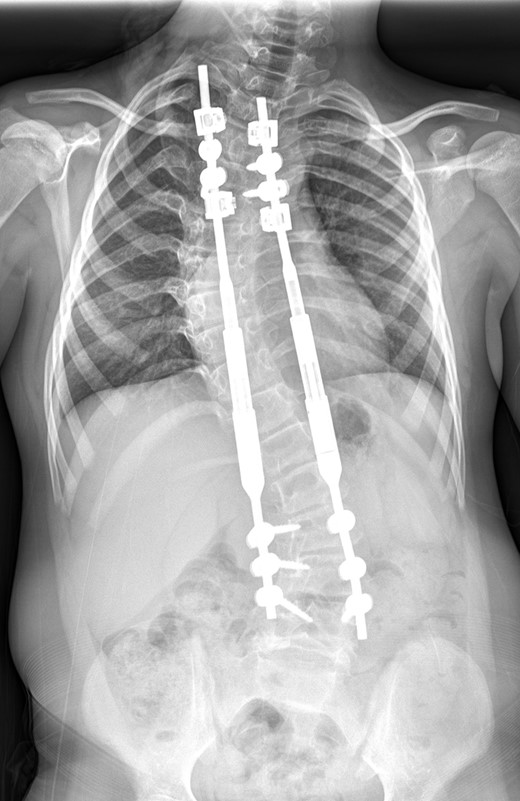

Between the ages of 4 and 6 years, the curve increased rapidly leading to a significant curve measuring 80° in the thoracic spine and 65° in the thoracolumbar spine with a T1–S1 height of 232 mm and T1–T12 height of 150 mm (Fig. 1). A decision was made to intervene operatively and posterior instrumentation with MCGR was performed. Special consideration was given to her bone fragility. Following 4.5 years of bisphosphonate therapy, her last bone mineral density (BMD) assessment by dual energy X-ray absorptiometry before surgery was normal. Her lumbar spine BMD Z-score was +1.5 and the total body less head BMD Z-score was also +1.5. Thus, at age 6 years, a construct of three paired sets of pedicle screws were placed at L2–L4 distally and a combination of pedicle screws at two levels (T4 and T5), with an outer square of sublaminar bands passed under the third and sixth ribs, was placed proximally. The instrumentation used was a 4.5 Expedium System (DePuy Synthes, Raynham, MA, USA) and the Silc Sublaminar Banding System (Globus Medical, Audubon, PA, USA). Post-operative radiographs (Fig. 2) showed good spinal balance and correction of deformity, but fractures of the right 5th and 10th ribs were seen posteriorly at the junction of the rib and transverse process. Following 8 weeks of spinal cast jacket protection, a CT scan showed the rib fractures to have healed. After instrumentation the thoracic curve angle measured 38° and the thoracolumbar curve measured 30°, with a T1–S1 height of 247 mm and a T1–T12 height of 160 mm.

A whole spine radiograph at age 6 demonstrating the double major scoliosis (measuring 80° in the thoracic curve and 65° in the thoracolumbar curve with a T1–S1 height of 232 mm and T1–T12 height of 150 mm).

An immediate post-operative whole spine radiograph demonstrating the spinal construct with the MCGR rods (measuring 38° in the thoracic curve and 30° the thoracolumbar curve with a T1–S1 height of 247 mm and a T1–T12 height of 160 mm).